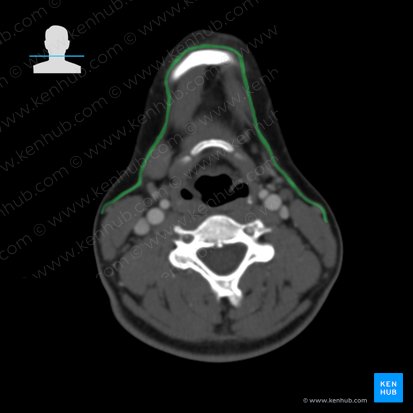

O platisma é um músculo par, plano e superficial do pescoço.

É considerado parte da musculatura mímica. O platisma se estende da pele da face desde discretamente acima das inserções da mandíbula até aproximadamente a altura da segunda costela. Ele segue cranialmente ao longo da face anterior do pescoço cruzando a clavícula.

O platisma é um músculo superficial e - ao contrário de outros músculos - diretamente conectado à pele. Ele cobre completamente ambos os lados da face anterior do pescoço. Em função de sua inserção na pele ele pode mudar a expressão facial junto com outros músculos faciais. O platisma pertence - assim como todos os outros músculos faciais - ao grupo da musculatura estriada.